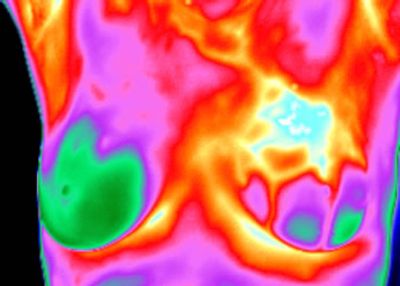

The first classification category in the Marseille system defines a normal thermal profile of the breasts that is devoid of any of the thermology signs or criteria associated with risk for breast cancer. All thermal features demonstrate normal and adaptive response to the autonomic challenge. Normal contours are discerned and no significantly hyperthermic focal or vascular features are presented. Some patients will demonstrate distinct and significantly hypothermic patterns that are frequently associated with established cysts and/or fibro-adenomas. This will modify the classification as a TH-1F. Annual comparative restudy is recommended.